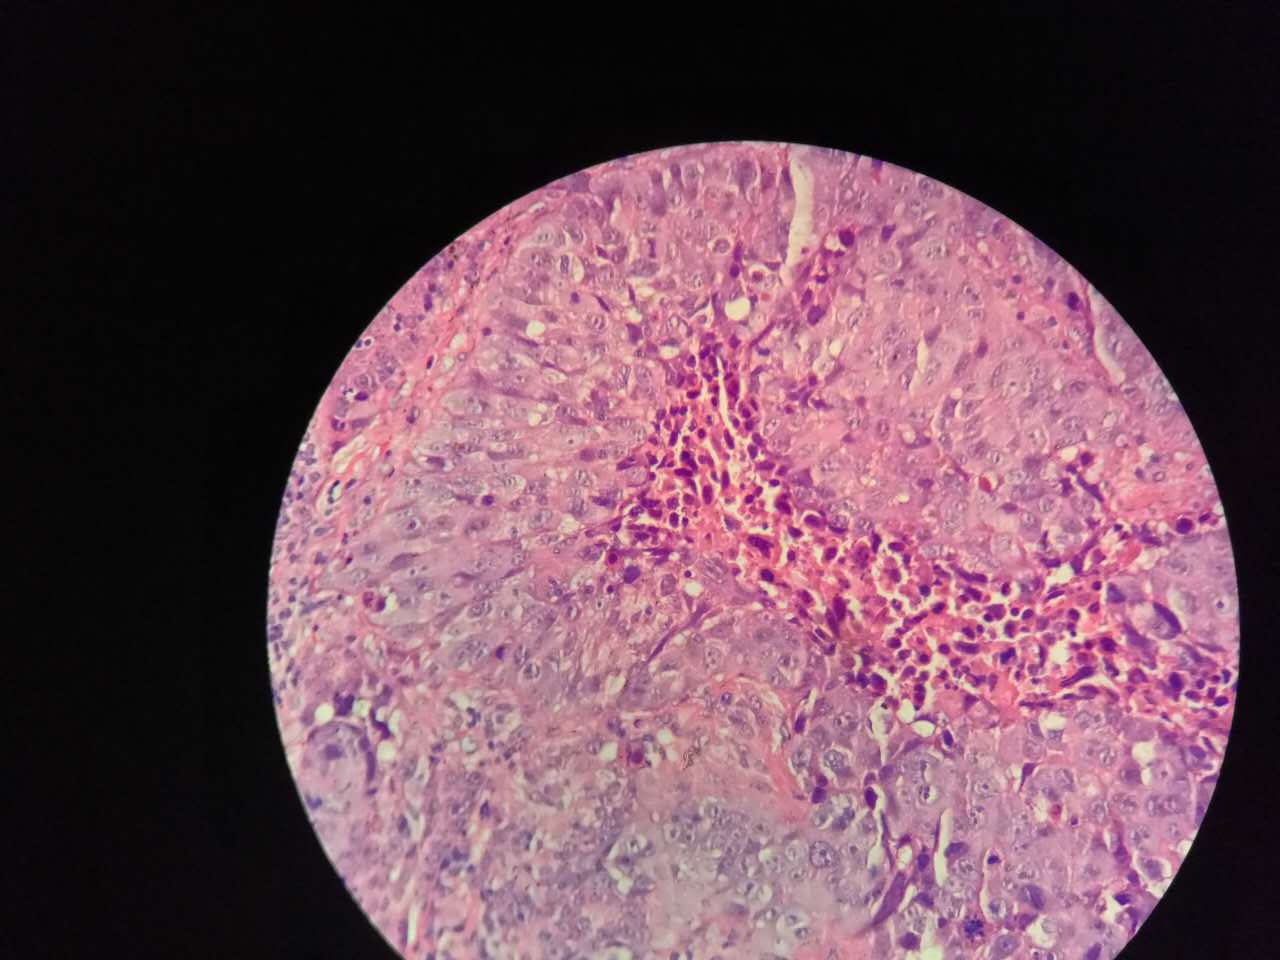

巢团可以很大,中央血供不足,就会坏死

中央红色的,有碎核

这个鳞癌不是早期

坏死也可以很大

较大的粉红区都是坏死,可以看出坏死是因为巢团大,中央坏死

下图是放大